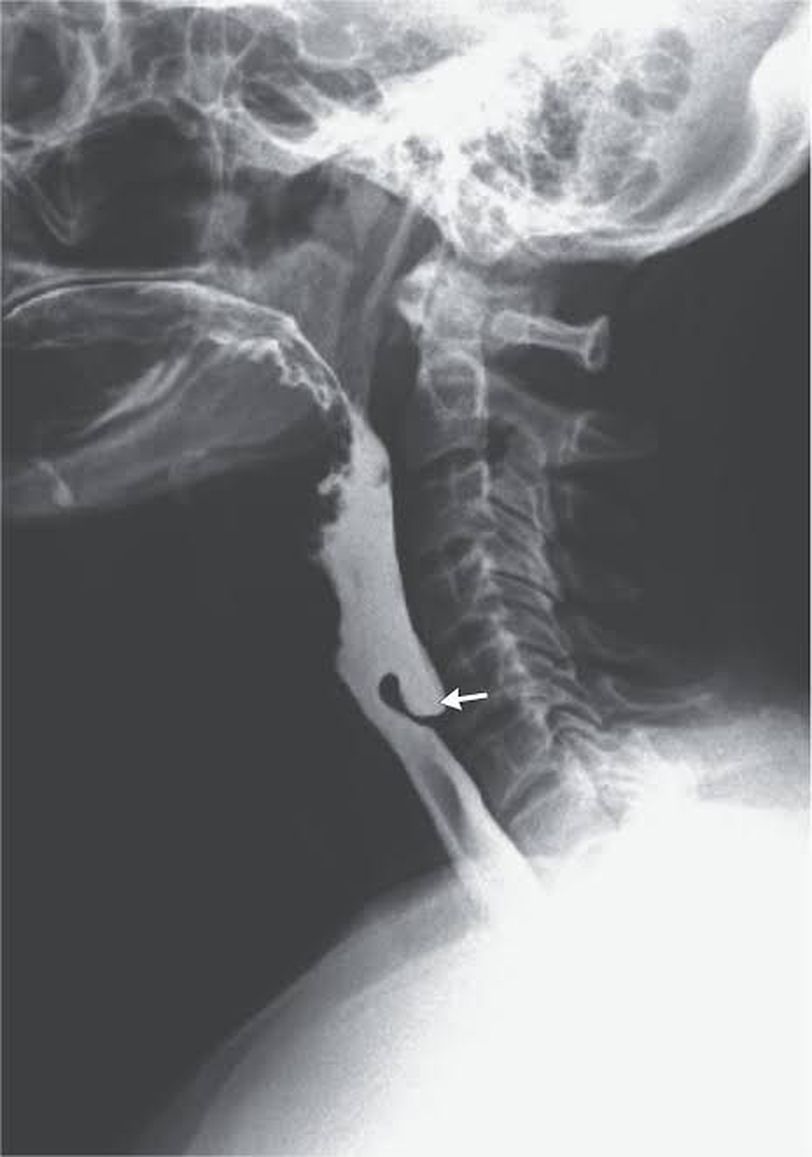

In the posterior pharyngeal wall, there is an inherent weakness between the two parts of the inferior constrictor muscle. This area is called the Killian's dehiscence and it lies between cricopharyngeus below and thyropharyngeus above. The pharyngeal mucosa can herniate through this weakened area and form the Zenker's diverticulum. Symptoms include dysphagia, regurgitation of undigested food and bouts of coughing especially at night. Patients also develop bad breath because of the constant presence of undigested food. Aspiration pneumonia may be a serious complication. The condition is diagnosed via endoscopy and barium swallow. The contrast can be seen filling a pouch behind the pharynx in the image above. Treatment is mainly surgical. It may involve excision of the pouch and separating it from the oesophagus either endoscopically or via cervical approach. Image via: https://www.nejm.org/doi/full/10.1056/NEJMicm1701620 Information via: Diseases of the ear, nose, throat and head and neck surgery- Dhingra, 6th edition